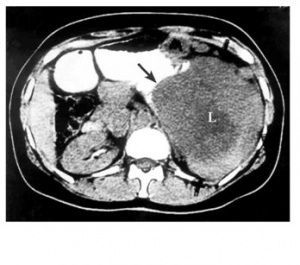

האבחנה יכולה להתבצע על-ידי בליעת בריום (תצלום 13.3), בטומוגרפיה ממוחשבת (תצלום 14.3 ו-15.3), או בגסטרוסקופיה (תמונה 9.3)